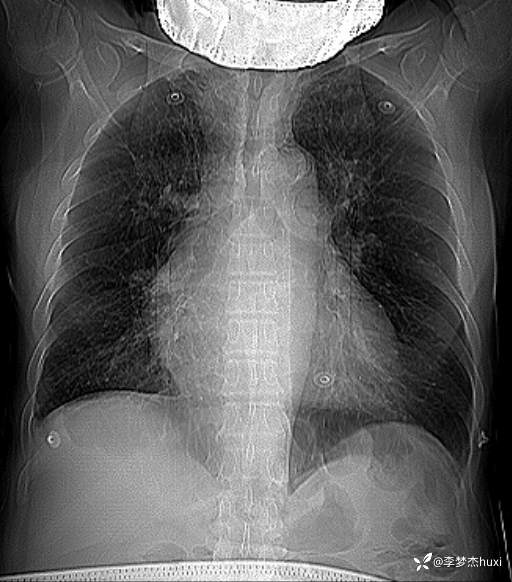

男, 82 岁,主因慢性咳喘20余年,患慢阻肺,平时喘息药物维持,半年前反复住院,并因为病重转上级医院治疗,自诉回家后做梦梦到自己换了一个狗肺,感觉从此不再喘息。